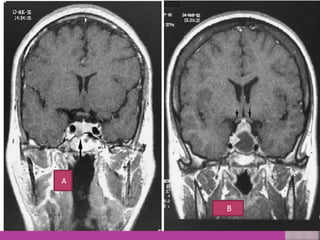

MRI---Pituitary adenoma (A) MRI– Pituitary fosa after surgery of

MRI---Pituitary adenoma (A)MRI– Pituitary fosa after surgery of macroadenoma empty Fosa